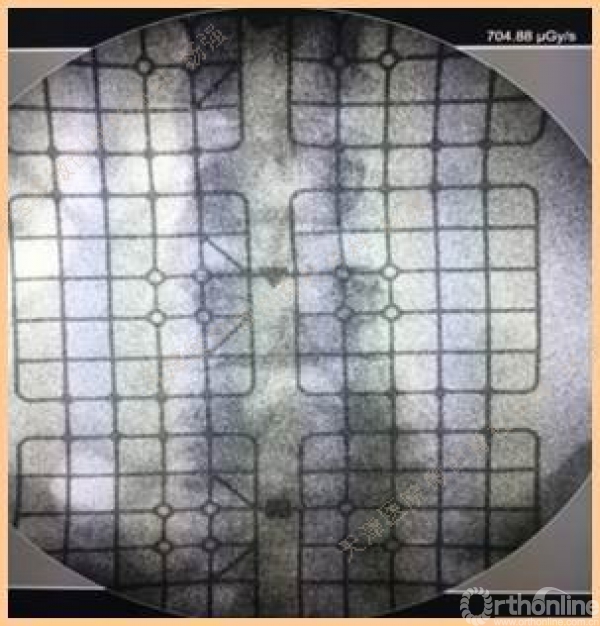

腰5椎体前滑脱I-II°,峡部裂,动力位显示腰5-骶1节段明显失稳